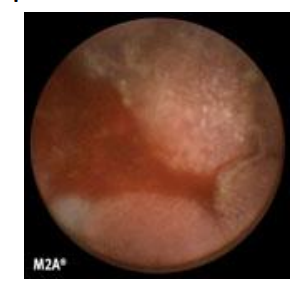

Capsule endoscopy

- is it commonly used?

- use

Capsule endoscopy

- available in few centres (expect as a research technique)

- use: to identify small bowel bleeding sites or if CT and mesenteric angiography are negative

*not usually used in acute setting and clinical practice